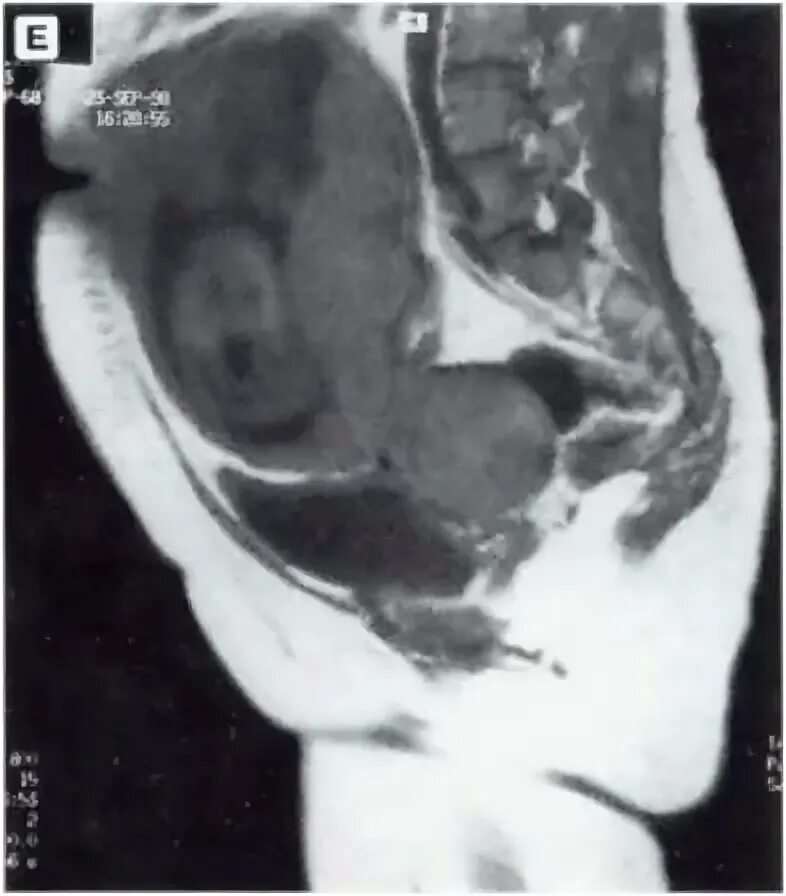

Солидное образование в малом тазу